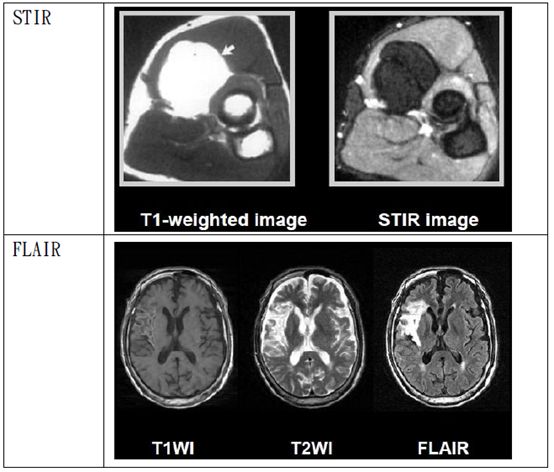

40.下列何者為磁振血管造影(MRA)最常用的成像波序? (A)spin echo (B)STIR (C)gradient echo (D)FLAIR